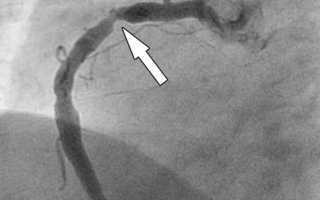

На сегодняшний день существуют различные методы исследования патологий сердечно-сосудистой системы, которые отличаются эффективностью и стоимостью. Сегодня людей больше всего интересует стоимость коронографии сердца в Бакулева, так как эта методика является очень эффективным средством в арсенале современных кардиологов. Она представляет собой рентгенографический метод исследования, который дает возможность детально исследовать коронарную артерию, определить точное место сужения ее просвета атеросклеротической бляшкой, выяснить, какой характер и протяженность носит это сужение, то есть, своевременно диагностировать ишемическую болезнь и своевременно оказать помощь больному. Обычно эта медицинская процедура назначается пациентам, которым в скором времени планируется проведение стентирования или шунтирования. В зависимости от результатов этого исследования и будет определена максимально подходящая операция для конкретного случая и для больного.

Коронография сердца — это важный диагностический метод, который позволяет врачам оценить состояние коронарных артерий и выявить наличие стенозов или других патологий. Специалисты подчеркивают, что данная процедура является ключевой для диагностики ишемической болезни сердца и других сердечно-сосудистых заболеваний. Во время коронографии в сосуды вводится контрастное вещество, что позволяет получить четкие изображения артерий на рентгеновских снимках. Врачи отмечают, что этот метод не только помогает в диагностике, но и может быть использован для планирования дальнейшего лечения, включая ангиопластику или установку стентов. Несмотря на минимальные риски, связанные с процедурой, специалисты рекомендуют ее проводить при наличии показаний, так как своевременная диагностика может существенно улучшить прогноз для пациента.

После того как пластиковая трубка будет установлена в артерии, через нее запускают специальное контрастное вещество, которое растекается плавно по ней. В это время врач тщательно следит за осуществлением процедуры и при помощи рентген аппарата производит соответствующие снимки. Исходя из того, что человек имеет две главнейших артерии, то катетер устанавливается сначала в одну, потом — в другую. Снимки делаются для каждой артерии под различными углами. Затем хирург проводит анализ полученных снимков и выясняет наличие и количество закупорок, а также сужение сосудов и их локализацию. Подробнее узнать о данной методике, а также увидеть ее проведение, можно, просмотрев видео, где показано, как делают коронографию сердца.